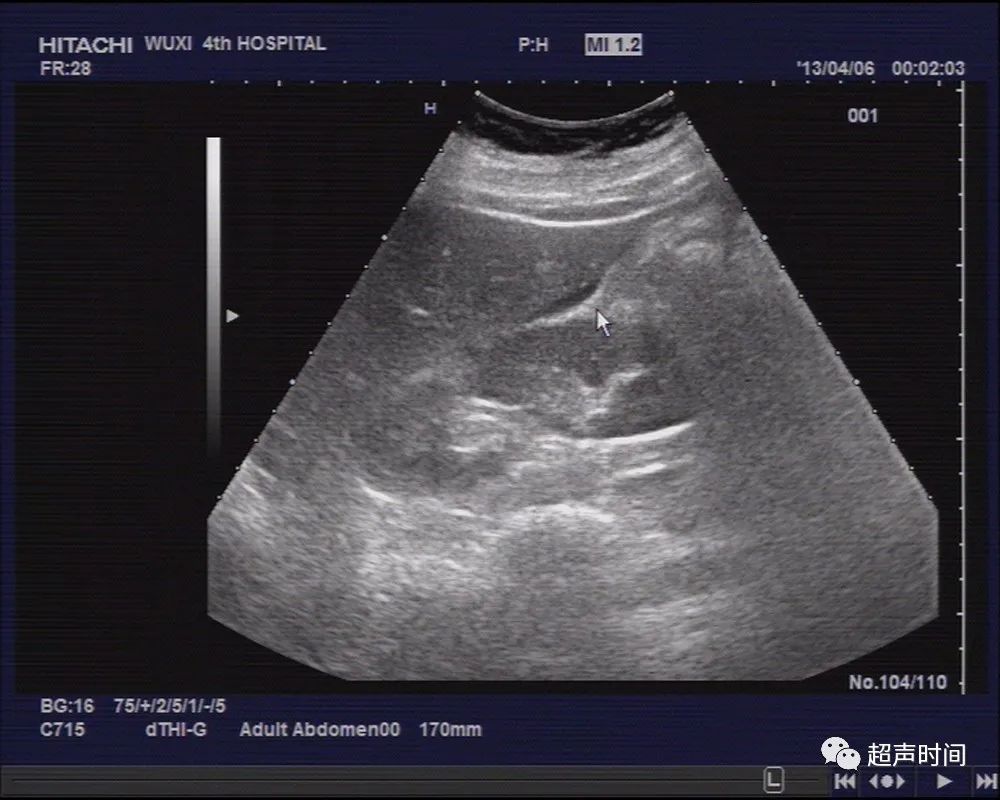

另于盆、腹腔探及液性暗区,最深约 30mm ,透声欠佳(图 3 ~ 5 )。

图 4 于肝肾间隙探及少量液性暗区